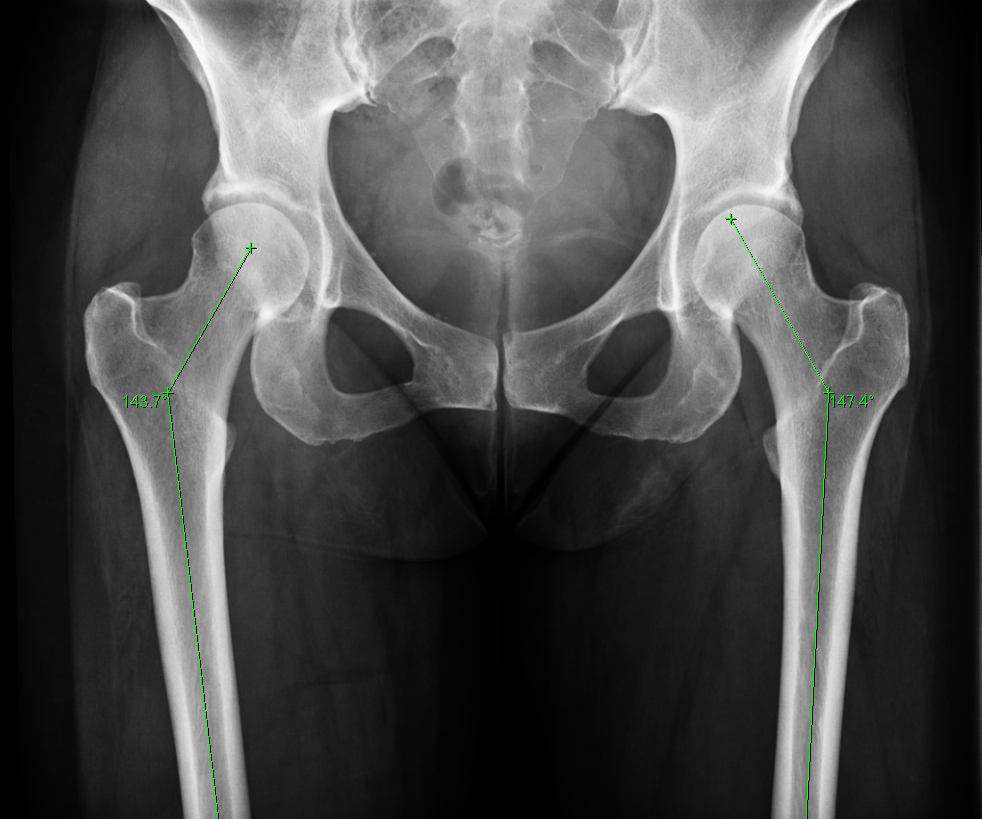

using the AP view of the hip, angle formed by axis of femoral shaft and line drawn along axis of femoral neck passing through center of head of femur ( RID2664 ) (figure 2). An example of coxa valgus is provided in the top image.

if < 125 degrees then coxa varus deformity ( RID4769 )

if > 135 degrees then coxa valgus deformity ( RID4768 )